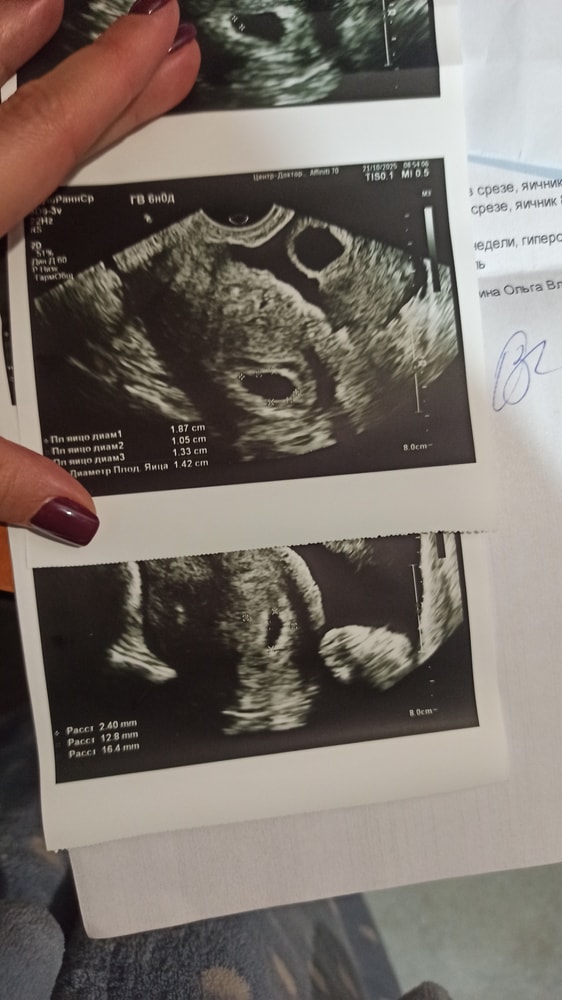

Привет, скопировала свои данные, правда на 22 дпп: 22 ДПП: ПЯ - 14 мм ЖМ - 4,5 мм КТР - 2,7 мм СБ +, ритмичное, ЧЧС - 115 уд.в минуту ❤️ Диагноз: прогрессирующая маточная беременность, 5-6 недель. *По месячным у меня 5н4д

24дпп было ПЯ -13мм, ЖМ-3.7. Но аппарат и врач очень достойные. В вашем случае- подождать надо однозначно и не расстраиваться раньше времени.

У меня на 23дпп плодное яйцо 13мм, жм 3 мм

Людмила Хасанова, ИзображениеВо втором якобы эмбрион, но он совсем маленький. Через живот ничего не было видно, потом вагинально посмотрела.